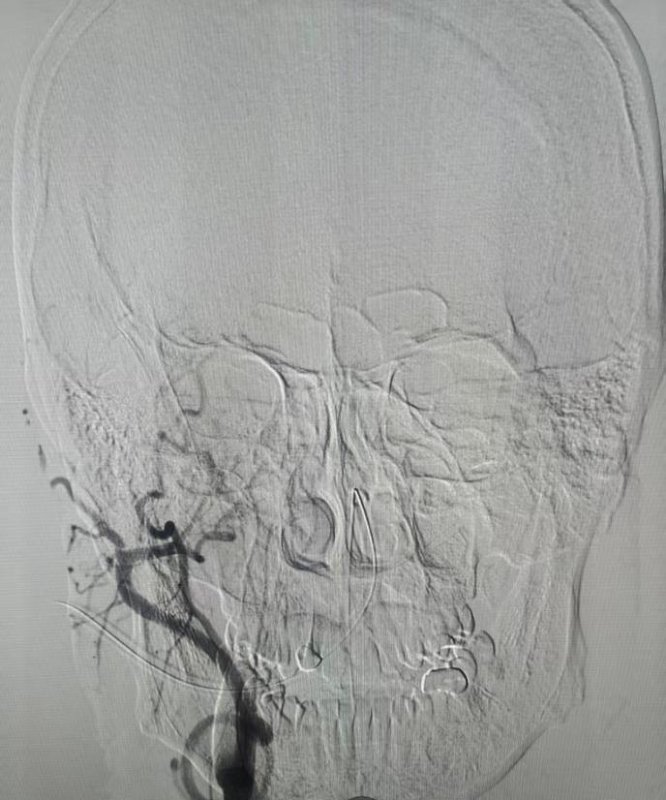

术前颈动脉闭塞

术后颈动脉成功开通

夹层远端继发血栓成功取出